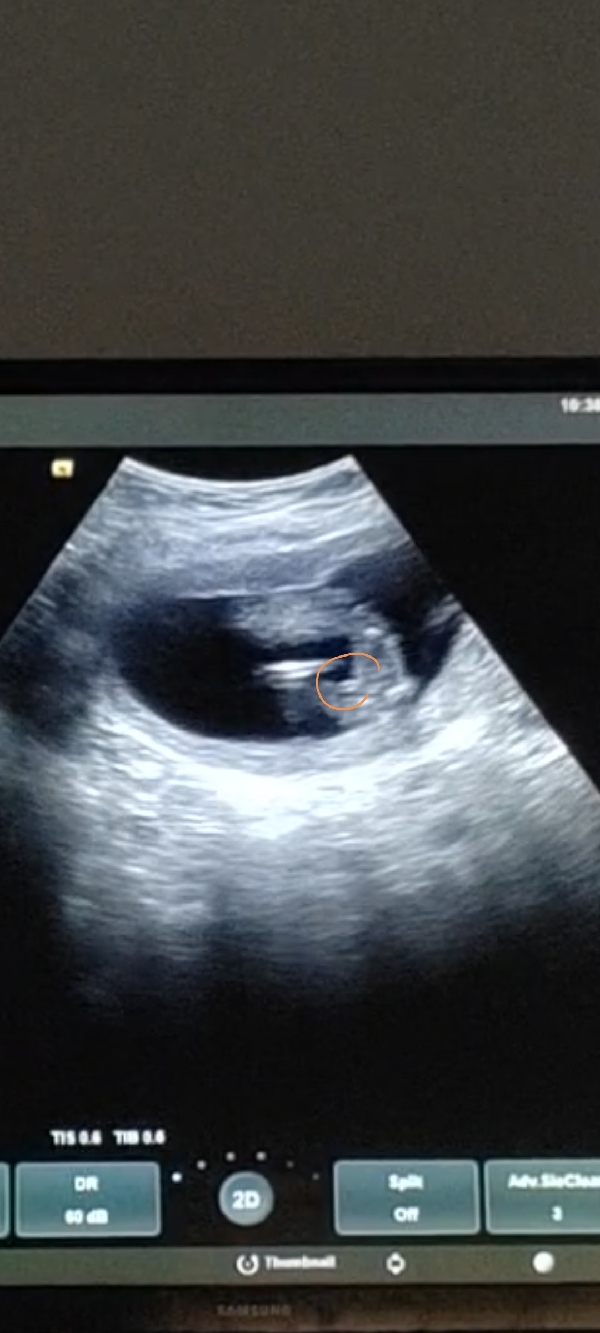

رحت للدكتورة بالأسبوع 14وقالت احتمال بنت لانه من تحت البيبي مو مبين حق ولد تقول مبين ٣ خطوط وعطتني موعد بعد اسبوعين تبغي تتأكد بس اني صورة فيديو ومبين كم لقطة من قدام و مفتوحة الرجل مادري تعرفون له لوو

اي هو مو مبين من تحت شي ولا في بروز وهاذي صورة من تحت مادري ليش قالت شاكة وبعد اسبوعين وبتتأكد قلت ليها اني بأول ولد ليي عطول بين عندي وعرفت انه ولد حتى قبل لاتقول الدكتورة يعني لو ولد مو معقولة مابيبين واني عندي ولدين